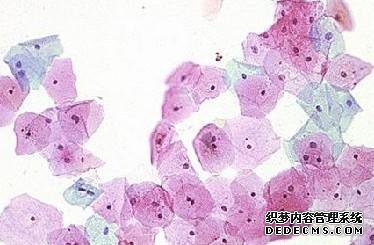

状态分析:宫颈分类是一种早期检测宫颈癌的简单有效的方法。

它能修复宫颈上皮细胞吗?去显微镜下观察建议:等级为1-正常。

Pap 2度-由于炎症引起的炎症细胞变化。

Bartholus 3-核异质性-可由炎症或肿瘤引起的严重细胞变化

Papse 4-可疑癌症-怀疑子宫颈癌。

确定子宫颈癌5级癌。